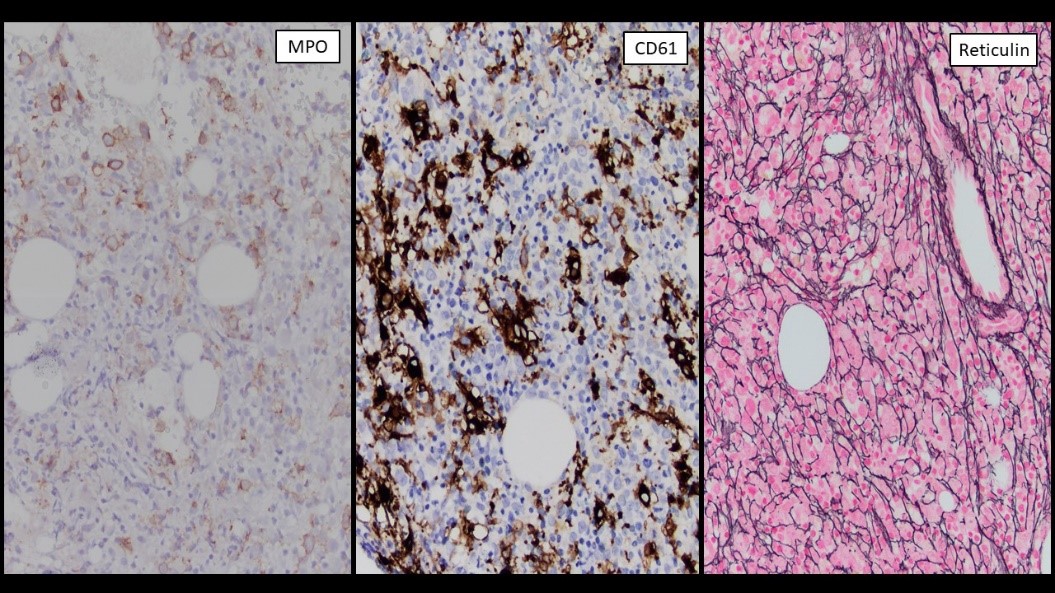

Megakaryoblasts are medium/large cells with dark blue vacuolated agranular cytoplasm. Cytoplasmic projections (blebs and pseudopods) resembling platelets, irregular cytoplasmic borders and cytoplasmic zoning maybe seen. Nuclei are round or slightly indented with finely reticular, dense chromatin and 1-3 nucleoli. Myelofibrosis or increased marrow reticulin is common fibrosis due to megakaryoblast secretion of fibrogenic cytokines, which makes marrow aspiration difficult.

CD41, CD61, CD42b, CD34, CD36, factor VIII and von Willebrand factor

Negative stains: Myeloperoxidase, Sudan Black B, CD14, CD64 and glycophorin A.